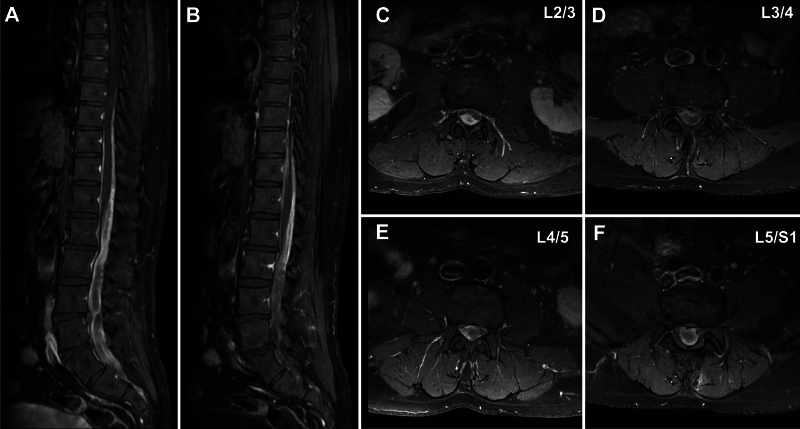

背景:脊髓硬膜外阻滞广泛应用于疼痛控制。虽然脑脊液渗漏或硬膜外血肿等并发症偶有报道,但硬膜外阻滞后的硬膜下血肿(SDH)是罕见的。据作者所知,涉及硬膜下和蛛网膜外腔的血肿以前没有报道过。观察:一名49岁男性,有慢性背痛病史,在常规腰硬膜外阻滞8天后出现严重的双侧腿感觉异常。MRI显示SDH从T8延伸至S3,压迫椎管背侧。通过L2-3和L5-S1半椎板切除术进行手术减压,随后行硬膜切开和Nelaton导管冲洗。患者术后症状完全缓解,3个月内血肿完全消退。经验教训:尽管脊髓硬膜外阻滞通常被认为是一种安全的手术,但罕见的并发症如SDH也会发生。对于硬膜外阻滞后未出现新的神经系统症状的患者,医生应高度警惕此类并发症。当诊断为SDH时,手术治疗包括椎板切除术和Nelaton导管冲洗可能是必要的,以优化患者的预后。https://thejns.org/doi/10.3171/CASE25448。

Observations: A 49-year-old man with a history of chronic back pain developed severe bilateral leg paresthesia 8 days after a routine lumbar epidural block. MRI revealed an SDH extending from T8 to S3, compressing the dorsal spinal canal. Surgical decompression was performed via hemilaminectomy at L2-3 and L5-S1, followed by durotomy and irrigation with a Nelaton catheter. The patient had full symptomatic relief postoperatively and showed complete hematoma resolution within 3 months.